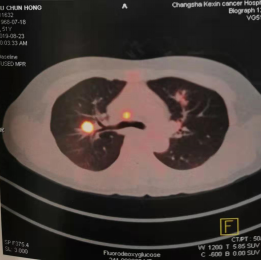

2019年8月(51岁),来院检测CT示肺部阴影,PET-CT示高代谢病灶。行超声支纤镜活检示:低分化鳞癌。

图2:2019年8月23日CT及PET-CT结果

PET-CT: 2019/8/23

(靶向治疗前)